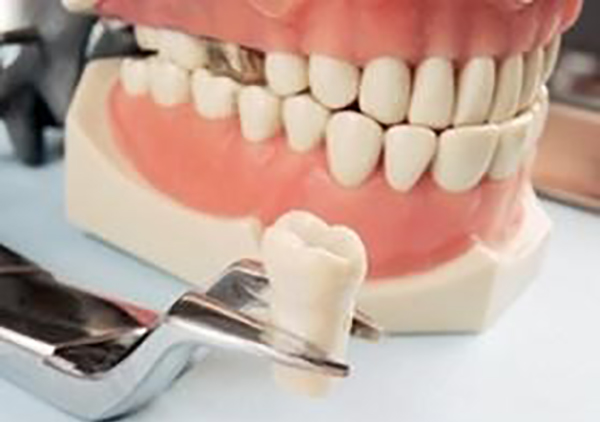

Перечень стоматологических услуг, оказываемых в нашей клинике, достаточно широк и включает в себя все виды зубоврачебных услуг, существующих на сегодняшний день. Все услуги, начиная от самых простых, как, к примеру, установка пломбы, и заканчивая самыми сложными, такими как имплантация, протезирование и т. п.

- Имплантация — операция, в процессе которой штифт устанавливается в зубную кость. Эта отрасль стоматологии развивается и совершенствуется с каждым годом. К сожалению, человеческие зубы не обладают способностью к самовосстановлению, поэтом имплантация применяется в следующих случаях:

- у пациента отсутствует один зуб;

- пациент потерял несколько зубов;

- у пациента полностью отсутствуют зубы.